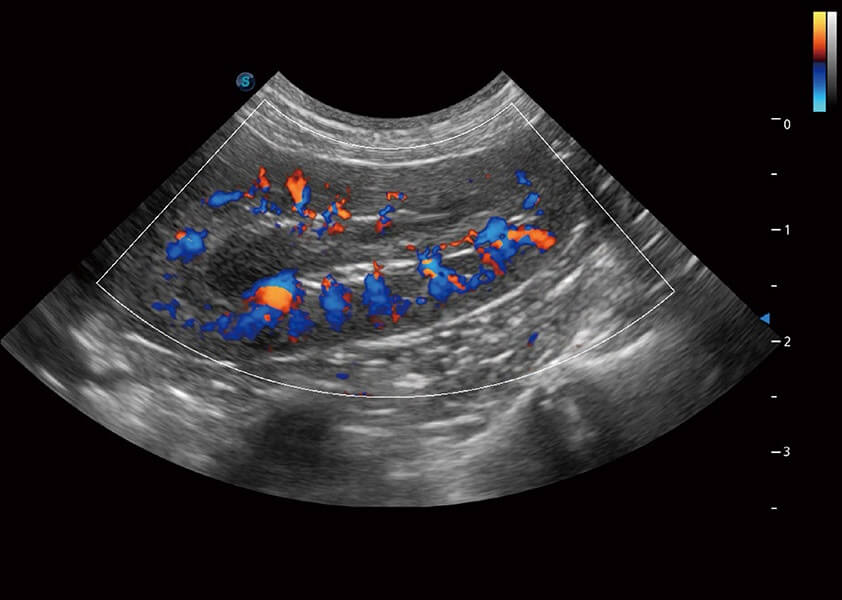

4T血流成像 微察秋毫

融合不同血流成像技术的优势,即可以提升血流成束性,同时可提高血流的视觉敏感性。

PDI 能量多普勒血流

提供高灵敏度和空间分辦率的血流图像,获得更加真实和丰富的诊断信息。

SR Flow 高分辨率血流成像

能够清晰显示细小、低速血流图像,获取传统彩色多普勒技术难以得到的细节和信息。

Micro F 显微血流成像

通过创新的Matrix E自适应滤波器和超长时间域算法,极大提升超低速微细血流的检出能力,同时更精准地滤除软组织和噪声信号,为兽用医生提供以往无法通过常规血流获得的疾病诊断信息。

Bright Flow 立体血流成像

在传统二维血流成像的基础上,呈现血流的立体感,具有动感的生命力之美。精确区分不同血管的空间关系,提高了血流的视觉敏感性。

优异的基础图像

(犬)肾脏血流